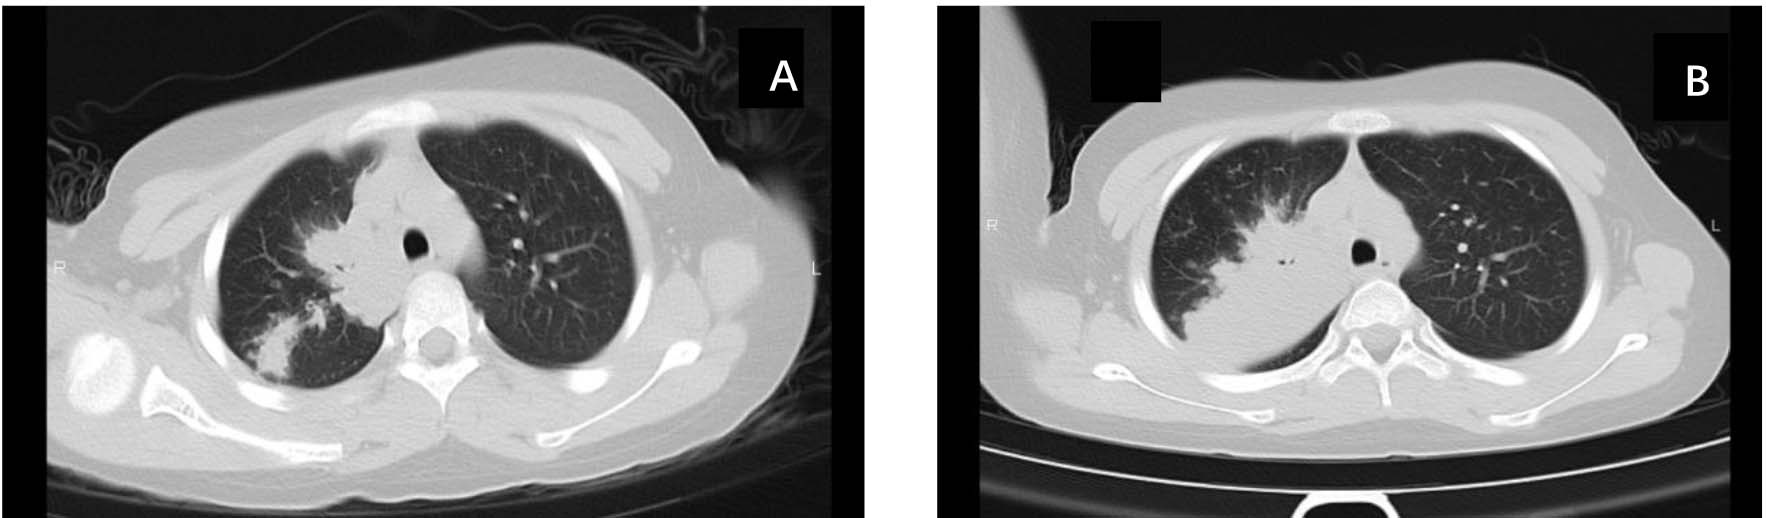

CT评分举例如下:图1图2显示两个患儿入院时的肺部CT表现及接受大致相同治疗方案10~14天后,复查的胸部CT表现及CT评分。

Figure 2. Chest CT images and CT scoring criteria for MPP in a 6-year-old male pediatric patient

2. 6岁男性患儿,MPP肺部CT检查图像及CT评分标准

图2(C)所示,入院时肺部CT示右肺上叶约50%的区域斑片状阴影伴有肺实变(CT评分,4 + 1)。如图2(D)所示,治疗12天后复查肺CT示右肺上叶约30%的斑片状阴影,实变消散(CT评分,3)。